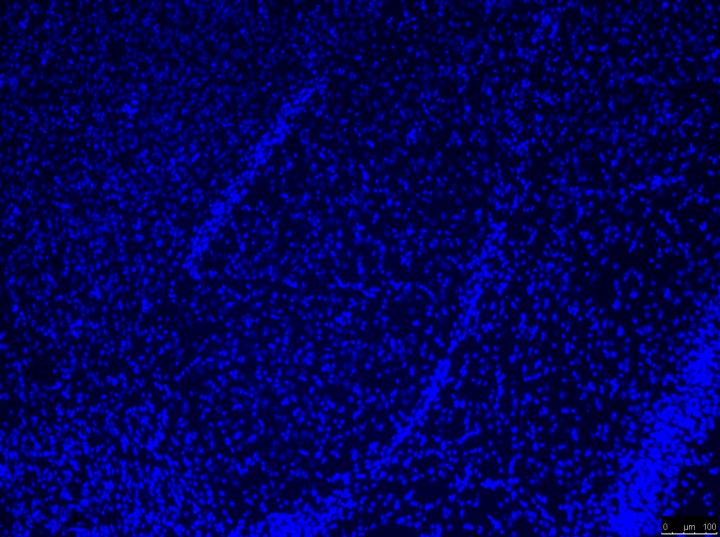

"Genetic analyses showed that mice with high levels of the expression of genes IL6 and PDYN in the amygdala were more sensitive to pain and these changes also correlate with personality traits", says Rafael Maldonado, full professor of Pharmacology at UPF's Department of Experimental and Health Sciences (DCEXS).These genes encode interleukin-6 and prodynorphin, proteins involved in inflammatory and pain sensitization processes, whose overexpression in neuropathic pain conditions had been previously reported in other areas of the nervous system such as the spinal cord.

Interestingly, the expression of these genes in the amygdala after nerve injury is influenced by personality traits. Thus, the anxiety trait enhances the expression of PDYN and IL6 in the amygdala, while the sociability trait correlates with a lower expression of PDYN. These data suggest that the impact of personality traits in the manifestations of neuropathic pain would be due, in part, to the modulation of gene expression in the amygdala.